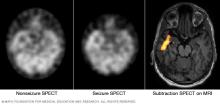

These SPECT images show the blood flow in the brain when there's no seizure activity (left) and during a seizure (middle). The subtraction SPECT coregistered to MRI (right) helps pinpoint the area of seizure activity by overlapping the SPECT results with brain MRI results.

• Single-photon emission computerized tomography (SPECT). This type of test is used if MRI and EEG didn't pinpoint the location in the brain where the seizures start.

A SPECT test uses a small amount of low-dose radioactive material. The material is injected into a vein to create a detailed, 3D map of blood flow during seizures. Areas of higher than typical blood flow may indicate areas where seizures occur.

Another type of SPECT test called subtraction ictal SPECT coregistered to MRI (SISCOM) may provide even more-detailed results. The test overlaps the SPECT results with brain MRI results.